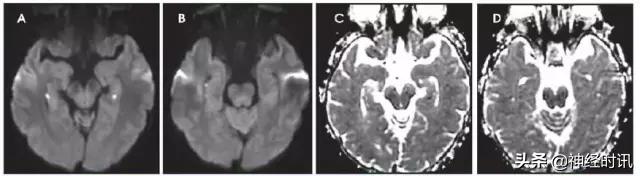

Wernicke脑病

Wernicke脑病见于伴硫胺素缺乏的嗜酒和其它营养不良患者。患者出现精神状态改变、记忆损伤、眼肌麻痹或共济失调。典型MRI显示乳头体、下丘脑、内侧丘脑、顶盖和导水管周围区域对称性T2/FLAIR高信号,大脑皮质也可能受累。在疾病早期,可见到由于细胞源性水肿导致的弥散受限(图8)。

图8 一例62岁女性,复视3个月,听力丧失数天,因眩晕、恶心、呕吐、眼震和厌食来诊。她被诊断为营养缺乏导致的Wernicke病,硫胺素水平为35 nmol/L (正常70–180)。MRI显示四叠体板、中脑导水管周围灰质、下丘脑和双侧上丘FLAIR高信号和各种不同程度的弥散(A:DWI,B:ADC)。